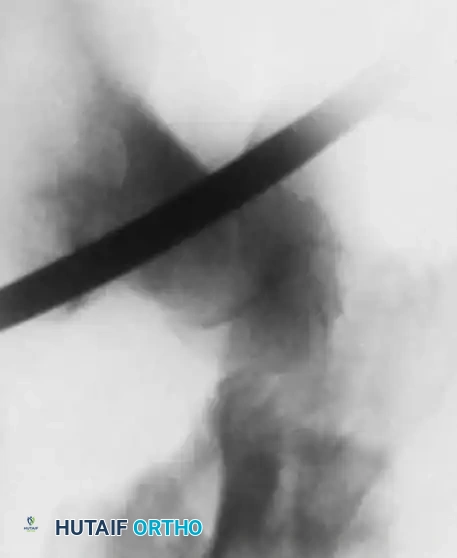

Fig. 9: Intraoperative fluoroscopy confirming pin placement across the physis.

Fig. 12: Lateral fluoroscopic view confirming central placement of the screws within the femoral neck.